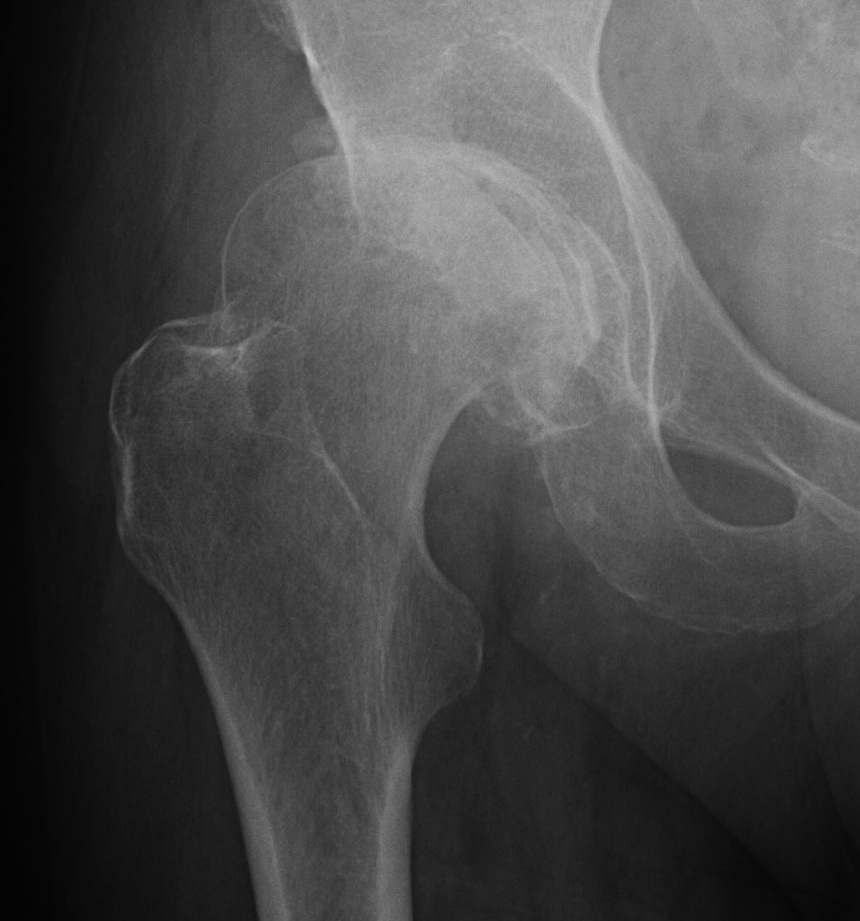

| Femur | Acetabulum | Leg Length Discrepancy | Abductors |

|---|---|---|---|

|

Multiplanar deformity |

Element dysplasia | 2 - 4 cm | Shortened |

| Worsened by previous surgery | May need trochanteric slide | ||

| Risk of intra-operative fracture | |||

| May require osteotomy |

Shallow acetabulum